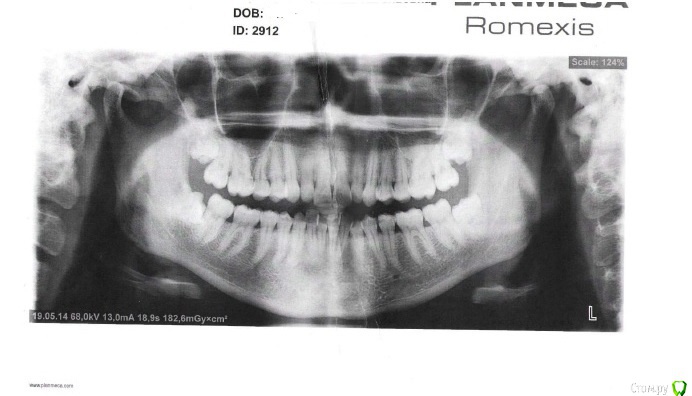

Удаление 8-к, кальцинированная эмаль

Возраст  - 28 лет.

Была на консультациях 2-х ортодонтов.

Оба настаивают на удалении лежачей нижней 8-ки перед установкой брекет-системы.На удалении остальных 8-х не настаивают.

1) необходимо ли удалять остальные 8-ки перед установкой брекетов?

2) Есть ли вероятность, что в процессе ношения брекет-системы, потребуется удалить еще какие-то здоровые зубы?

3) с моей "кальцинированной" (так сказал стоматолог-терапевт) эмалью можно ли вообще устанавливать брекеты? Не станет ли при должной гигиене их состояние хуже, чем до лечения?